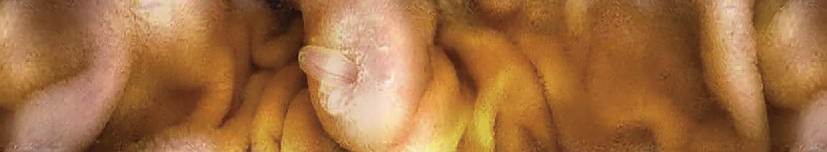

図2 CapsoCam® plusで撮影された乳頭部付近の画像 (広瀬産業株式会社提供).